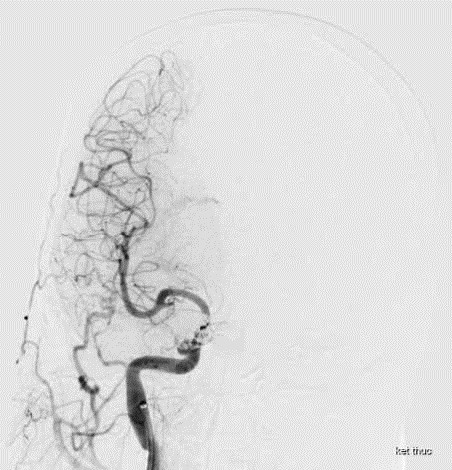

Sau khi thăm khám, thực hiện các xét nghiệm bao gồm chụp CT mạch máu não và chụp mạch máu số hóa xóa nền (DSA), bệnh nhân được chẩn đoán bị dò động mạch cảnh – xoang hang (Carotid-Cavernous Fistula - CCF). Đây là hiện tượng xuất hiện lỗ dò động tĩnh mạch giữa động mạch cảnh và xoang hang, khiến thay đổi các dòng dẫn lưu máu tại xoang hang.

![]() |

| Hình ảnh rò động mạch cảnh xoang hang trên phim chụp - Ảnh BVCC |